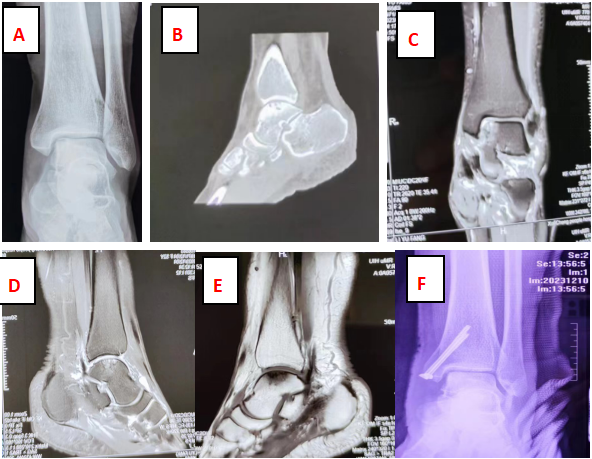

(圖A-E為術(shù)前X線(xiàn)、CT及MR表現(xiàn);圖F為術(shù)后X線(xiàn))

? 家住薛城的李女士,2年前不慎崴傷左腳,當(dāng)時(shí)未在意,未曾就醫(yī)診治,之后左足踝部?jī)?nèi)側(cè)經(jīng)常出現(xiàn)腫痛情況,休息后疼痛緩解,活動(dòng)后疼痛加重,近半月來(lái)左足踝部疼痛加重,休息也無(wú)明顯緩解,嚴(yán)重影響日常生活及工作。遂到我院手足外科就診,予以拍片檢查,初步考慮為“距骨骨軟骨損傷”,經(jīng)左踝部三維CT及MRI進(jìn)一步檢查后明確診斷為:左距骨骨軟骨損傷,距骨骨囊腫。

12月9日,我院手足外科為其做了“經(jīng)內(nèi)踝截骨、距骨骨囊腫病損切除+骨軟骨移植修復(fù)術(shù)”,術(shù)后6天疼痛緩解,順利出院。

患者到醫(yī)院就診時(shí),醫(yī)生首先會(huì)為患者拍個(gè)踝關(guān)節(jié)X線(xiàn)片。踝關(guān)節(jié)X線(xiàn)片常常在距骨的內(nèi)上角或外上角發(fā)現(xiàn)低密度改變。但X線(xiàn)檢查對(duì)于較輕的、軟骨下骨無(wú)明顯破壞的距骨骨軟骨損傷檢出率不高,容易漏診。CT檢查相對(duì)于X線(xiàn)檢查而言更細(xì)致,CT檢查能夠進(jìn)行三維成像,可以更加直觀(guān)的顯示軟骨剝脫的具體情況,是其他檢查無(wú)法實(shí)現(xiàn)的。但CT沒(méi)有MR敏感,如果僅僅是軟骨損傷,CT檢查也可能無(wú)法發(fā)現(xiàn)。為了避免漏診,這時(shí)做個(gè)MR檢查是必須的。MR檢查能夠發(fā)現(xiàn)X線(xiàn)及CT無(wú)法發(fā)現(xiàn)的軟骨和軟骨下骨的隱匿損傷,同時(shí)還能夠診斷出是否合并有韌帶,可以更準(zhǔn)確的顯示出關(guān)節(jié)軟骨損傷的面積大小以及受傷深度等情況,為進(jìn)一步治療提供依據(jù)。